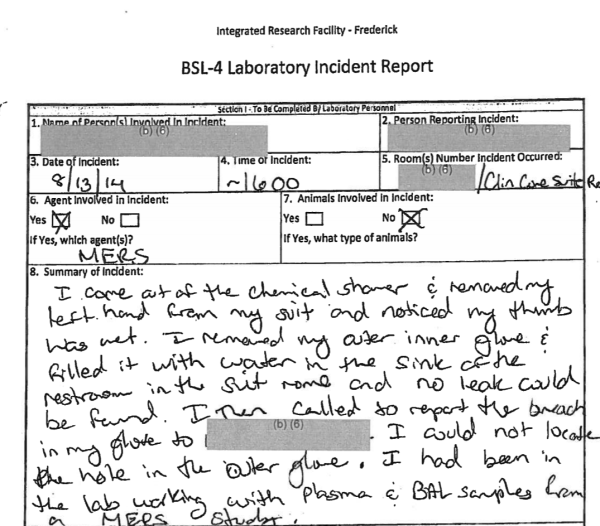

然而,不论是IRF-Frederick还是USAMRIID,这两个在德特里克堡内研究包括SARS和MERS在内的,危险冠状病毒的美国官方和美军科研机构,却都存在着差劲的实验室安全记录。

先来看IRF-Frederick的情况。美国《弗雷德里克新闻邮报》一份2014年的公开资料就显示,IRF-Frederick虽然号称有着安全等级很高的BSL-4生物实验室,也就是我们国内所说的P4实验室,但仅在2014年一年,这里就出现过多起实验室安全事故,而且一些事故还直接涉及MERS这样的高危冠状病毒。

同时,IRF-Frederick的其他较低安全等级的实验室,也同样被曝出存在实验室安全问题。

(来源:https://bloximages.newyork1.vip.townnews.com/fredericknewspost.com/content/tncms/assets/v3/editorial/7/87/7874b5b2-92b9-11e4-bc44-5b2aa5246268/54a6f8646aa25.pdf.pdf)